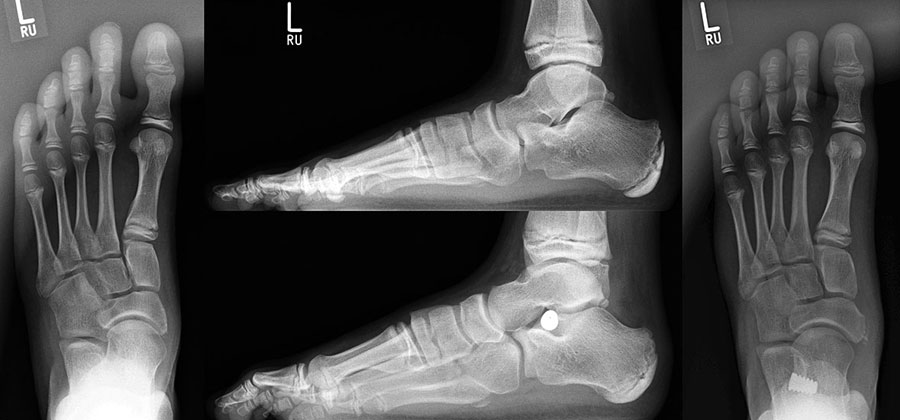

Radiologische Beurteilungsparameter sind im belasteten seitlichen Strahlengang der Talo-Metatarsale-I-Winkel (Meary`s angle), der Calcaneusneigungswinkel (Calcaneus pitch), der Talusneigungswinkel, der Costa-Bartani-Winkel und der Talo-calcaneare Winkel. In der d.p.-Belastungsaufnahme der talo-calcaneare Winkel (Kite angle), der talo-metatarsale Winkel und der talonaviculare Überdachungswinkel 191432056781918 (De Pellegrin 2007, Schröder 2006, Hamel 2010, Arnold 2010). Hamel bietet mit seinem additiven TMT-Index eine radiologische, quantifizierbare Vergleichsmöglichkeit bei dreidimensionaler Erfassung der Fehlstellung (Hamel 2006, Hamel 2010, Kuhn H 2010, Arnold 2010).

• Röntgenaufnahme des Fußes unter Belastung in dorsoplantarem, seitlichem und schrägem Strahlengang.

• Beurteilung der Form des Längsgewölbes und des Taluskopf-Containments sowie der oben angeführten messbaren Parameter.

Röntgenkontrolle d.p. und seitlich unter Belastung nach 2, 6 und 12 Wochen und Beurteilung des Ergebnisses im Vergleich mit den präoperativen Bildern.

• Röntgenkontrolle d.p. und seitlich unter Belastung nach 2, 6 und 12 Wochen und Beurteilung des Ergebnisses im Vergleich mit den präoperativen Bildern (Abb.15).